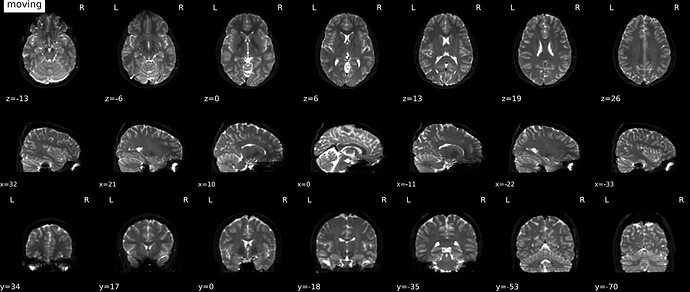

Should the masked (skull-stripped) B0 reference image be used in the alignment of the reference EPI image to the anatomical reference (coregistration)? The gif in the .html output shows a non-masked B0 image (eyeballs can be seen), even though the gif in the B=0 Reference Image step shows good masking. I also do not see the blue and cyan indicators in the b=0 reference gif, nor the red contour in the coregistration gif.